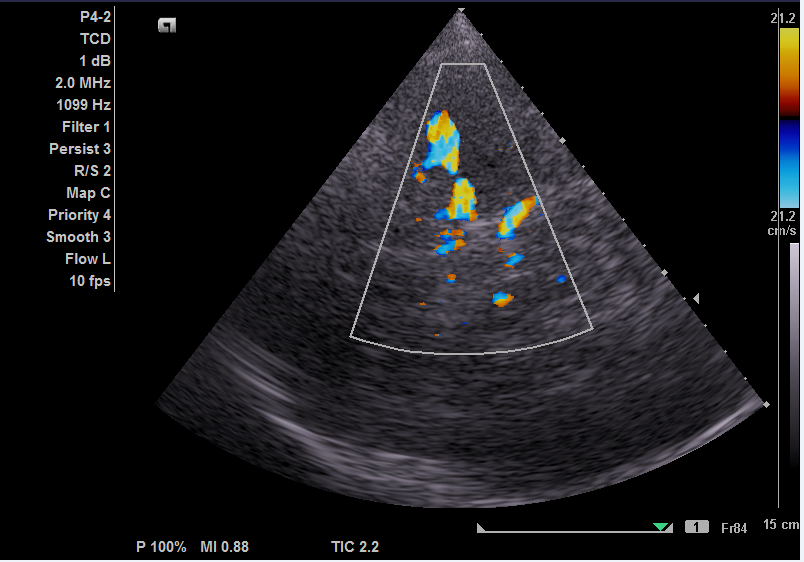

The examination is performed with a sector transducer through 'cranial windows', as these are the areas where bones of the skull are thinner and allow the best transmission of ultrasound. On the side of device, a good penetrating ability is provided by a stream of waves with low frequency. Since the higher the frequency, the faster the ultrasound wave attenuates, it is best to use transducers with a frequency of 1-6 MHz.

However, in order to obtain a diagnostically-appropriate image, one sensor with the appropriate frequency is not enough. You also need a machine with a good power which allows us to obtain an image with acceptable 2D resolution and high color Doppler sensitivity. We all know that machines are divided into different classes. In this article, we want to show you that for a good head vascular examination, it is not necessary to choose a premium class machine with an exorbitant price.

They are proven to be expert class machines that demonstrate their ability in all types of examinations. This image is from Toshiba Aplio 300. Generally speaking, the wide range of functions of this company's machines allows us to achieve the image option that best suits the doctor. Those who have encountered images from different brands will understand.